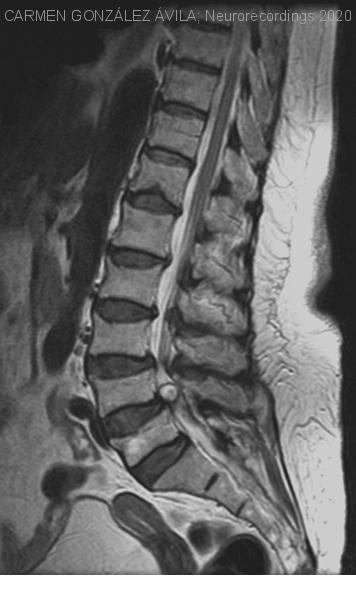

Quiste sinovial como causa de un síndrome de cola de caballo.

Mujer | 76 años

Diagnóstico final: Quiste sinovial lumbar.

Mujer de 76 años sin antecedentes de interés.

Acudió a urgencias por cuadro de 24 horas de evolución de parestesias en calcetín en miembros inferiores y dificultad para la deambulación. Asociaba incontinencia urinaria y estreñimiento. Refería además lumbociatalgia...